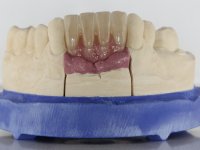

Após estudo imagiológico foi planificada a colocação de dois implantes de 3.3 mm de diâmetro e 10 mm de comprimento. No dia da cirurgia foram extraídos os dentes 42 e 32 e removido o implante. Os implantes foram colocados na zona dos alvéolos tendo o cuidado de lingualizar um pouco o seu posicionamento. Foi feita uma impressão pela técnica de moldeira aberta com o retalho aberto para a confeção da ponte provisória imediata. Enquanto a impressão foi para o laboratório, foram colocados parafusos de cicatrização altos e feita a sutura da ferida cirúrgica. A paciente esperou 2 horas na sala de espera enquanto no laboratório era confecionada a ponte provisória. A ponte provisória imediata aparafusada foi colocada e o seu assentamento controlado imagiologicmente. Passados 3 meses foi realizada a impressão definitiva com uma técnica de moldeira aberta. Nessa consulta aproveitamos para polir a ponte provisória com taças de borracha para que os tecidos moles pudessem maturar em melhores condições. Foi feita a recolha de informação para caracterizar da melhor forma a estrutura monolítica em Zr. Foram utilizadas guias de cor para a cerâmica de tonalidade coronária e gengival. No laboratório foi confecionada uma ponte em Zr. aparafusada que foi cuidadosamente caracterizada. Após aprovação pela paciente foi colocada definitivamente em boca. O aperto foi feito com uma chave dinâmica com 35 N de torque. Os orifícios foram tapados com teflon e obturados com resina composta.